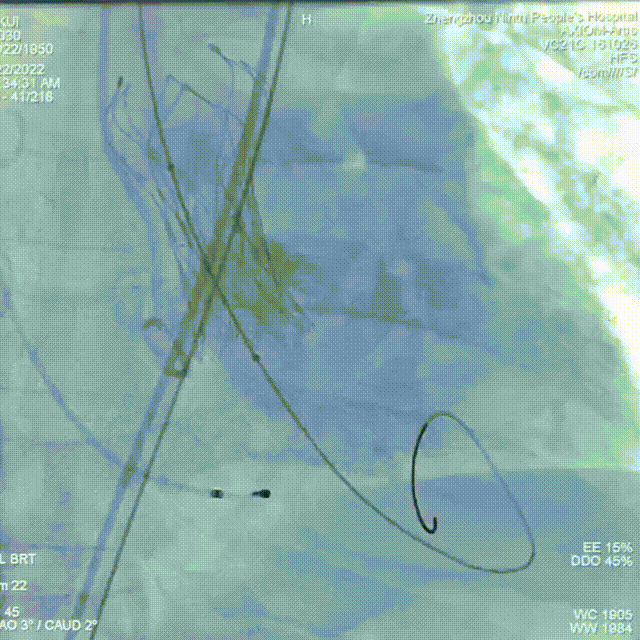

瓣膜脱钩释放

22mm球囊后扩